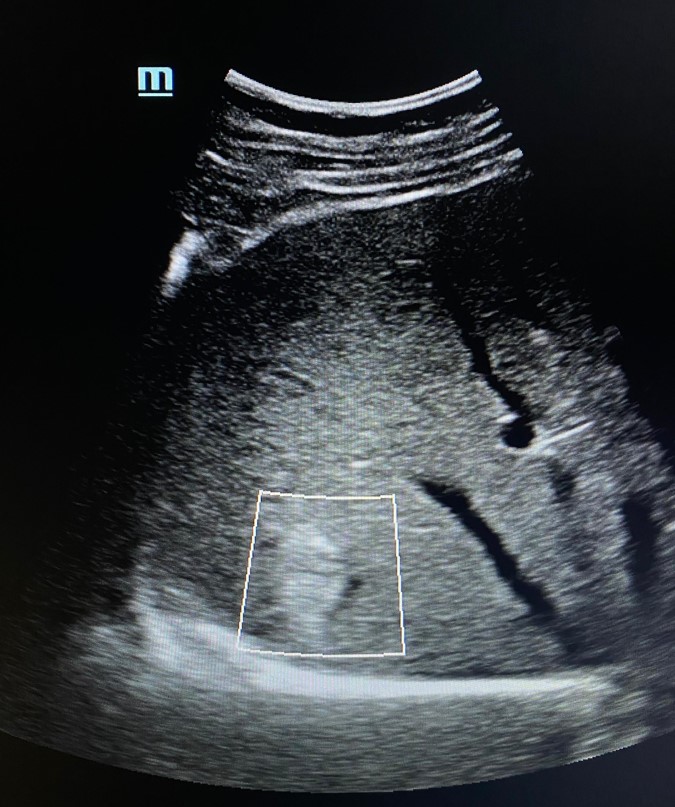

Como hallazgos, se aprecia un aumento moderado y difuso de la ecogenicidad hepática, ya descrito en ecografías previas, además de algunas áreas más hipoecoicas de límites geográficos en cara anterior de la bifurcación portal que pudieran corresponder a zonas de parénquima libre de grasa. Pero además, en el lóbulo hepático derecho, se aprecia una LOE solitaria hiperecogénica, de bordes irregulares, bien delimitada, con un halo hipoecoico y con registro Doppler negativo.